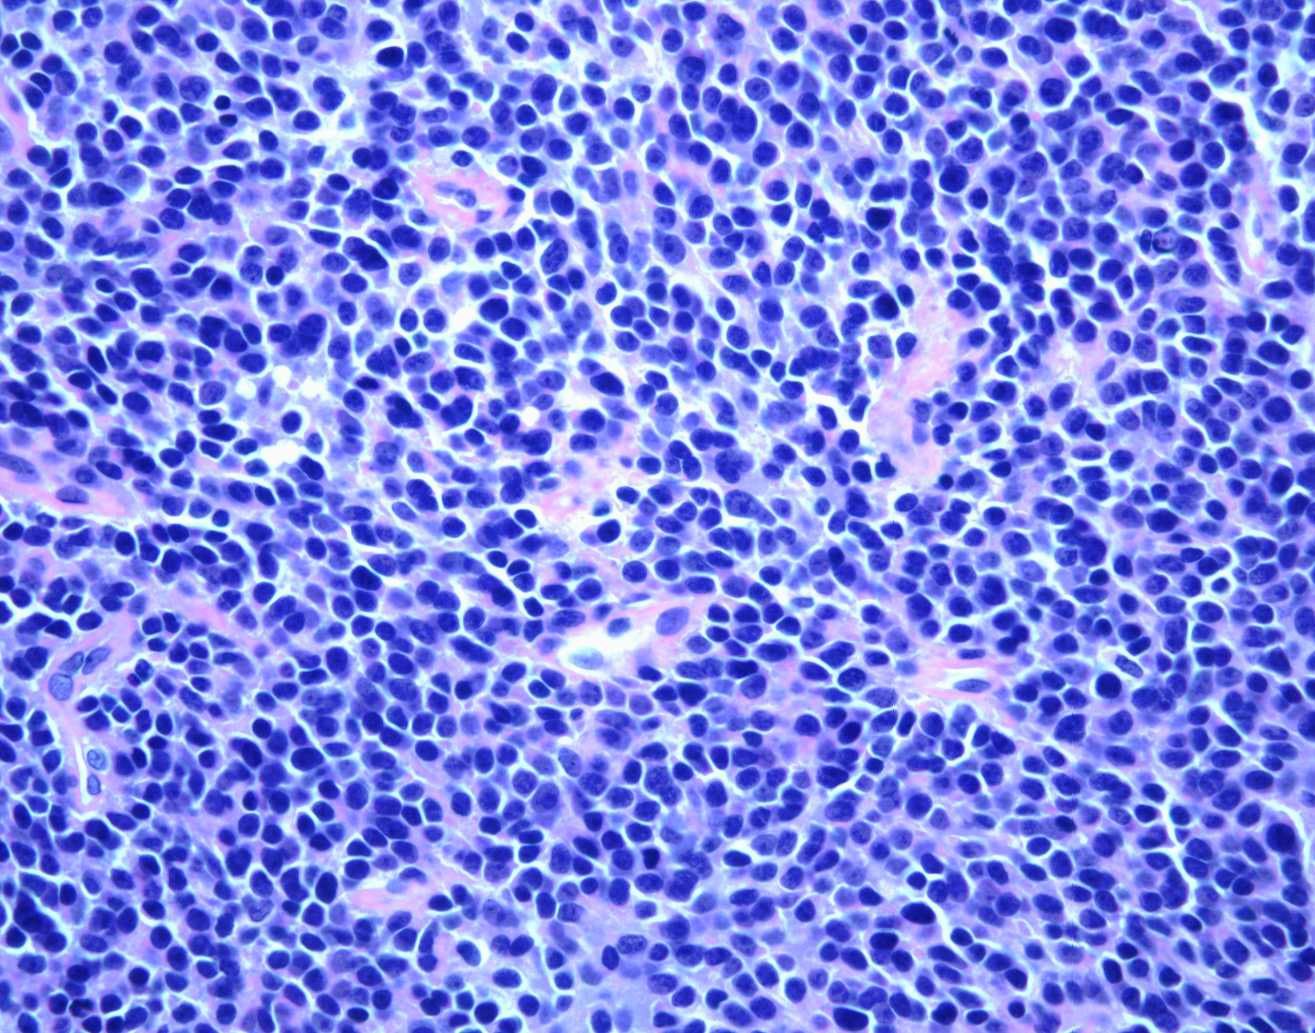

Ewing sarcoma tumors are sometimes called small blue cell (round cell) tumors because of the way they look under a microscope.

Microscopic view of Ewing's sarcoma

The small, round, blue cells of Ewing sarcoma as seen under a microscope.

Reproduced from Domson G, Scarborough M, Gibbs CP: Malignant bone tumors in children. Orthopaedic Knowledge Online 2007. Accessed April 2019.